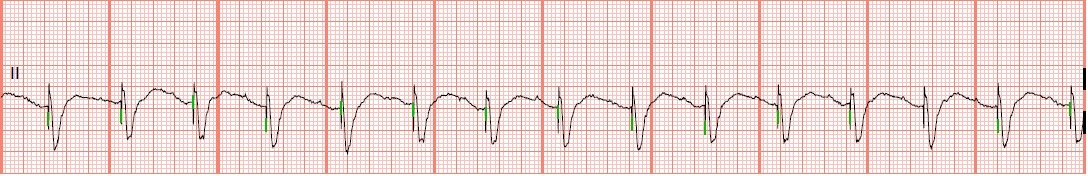

EKG Rhythm Strip Quiz 76

Identify the following rhythms.

1.

a. 1st degree block

b. Normal sinus rhythm

c. Sinus bradycardia

d. Accelerated junctional rhythm

1. a. 1st degree block